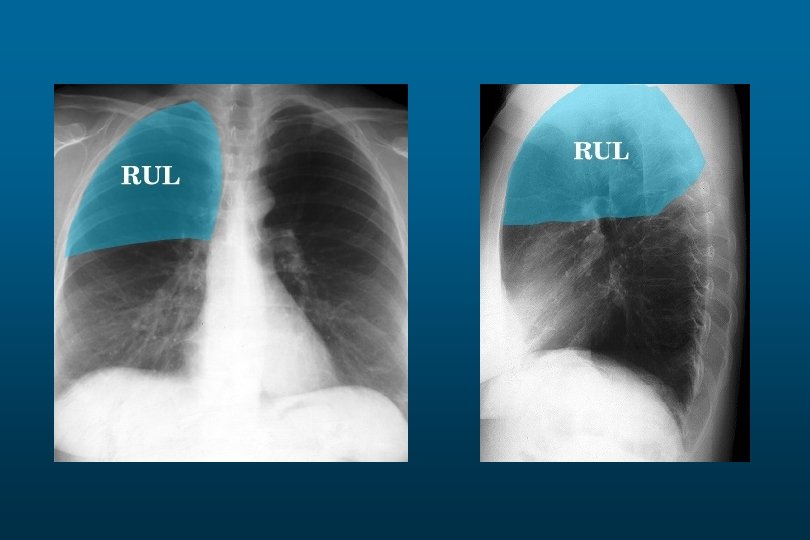

Right Upper Lobe Pneumonia